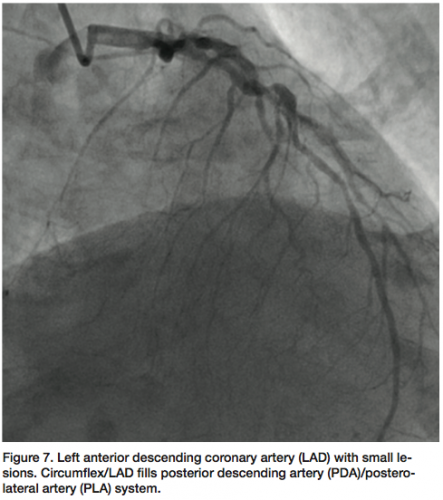

be totally occluded (probably chronic) (Figure 5) and a large posterior descending artery (PDA)/postero-lateral artery (PLA) system is noticed on angiography of the left arteries. The collaterals to the PDA/PLA appear to come from the left anterior descending coronary artery (LAD) and circumflex (Figure 6). The chronic total occlusion (CTO) appears moderate in length once the collateral and main vessels are visualized, with a calcific channel outlined.

The LAD shows “lumpidy-bumps,” but nothing more than a 70-80% (remember, it is subjective) lesion (Figure 7). There are smaller lesions throughout the artery. The circumflex has a lesion that could be repaired with angioplasty (Figure 8).

The discussion, in this case, was whether to fix the circumflex and bring the patient

back later to attempt to open the CTO in the RCA. Further review of the LAD angiograms elicited suspicion regarding the present lesions. If the lesions were not significant, the angioplasty would proceed; however, if the lesions were significant, the patient would be sent to surgery for at least a three-artery bypass.

Since IVUS would clearly show a calcium burden, which was somewhat visible on the angiograms, we used a pressure wire to determine the physiological status of the artery. We also felt it was possible that the IVUS catheter may not completely reach the lesions, or be able to pass through the tortuosity in the LAD.